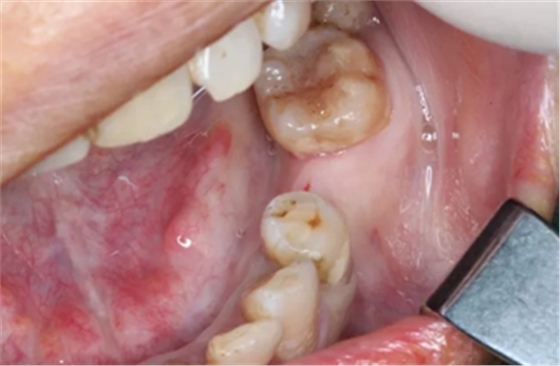

病例概述:48岁女性患者,口内健康状况良好,#35缺失多年,牙槽嵴顶骨宽度较窄。

#35缺失多年,导致#34向#35倾斜。

临牙间距不足,因此,对种植体的位置要求极高。